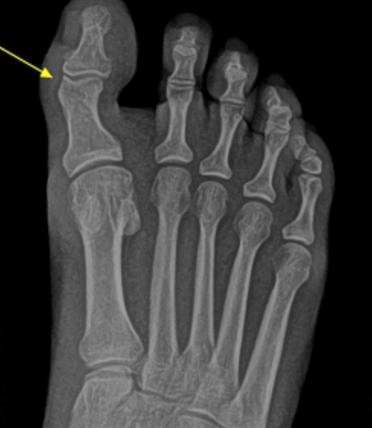

Oignon / Bunion Hallux Valgus

We practice surgery for bunions also called Hallux valgus. There exist more than one hundred different procedures for the correction of bunions. Often the procedure can be done with a minimal (very small) incision or a buried K-wire. These methods are advantageous because they are very effective, low risk, have shorter operating times and healing is more rapid. The Osteotomy (cut in the bone in the shape of a V) permits us to move the first metatarsal head giving better correction. Other bunion procedures which just remove the bump are less effective. In general bunion surgery takes about an hour to an hour and a half to perform and is performed under location anesthesia and mild sedation if necessary. The incision is frequently made on the side of the foot, which gives a better final appearance after healing.  The time for total healing is about 2 months.